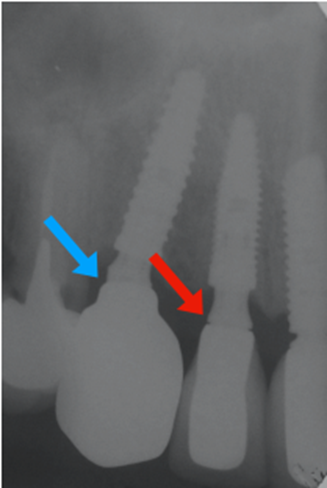

Na segunda consulta, a prótese parafusada metalfree foi instalada e aparafusada a 10 Ncm como recomendado pela fabricante. O orifício de acesso ao parafuso foi restaurado com resina fotopolimerizável e uma radiografia final foi realizada (Figuras 20, 21, 22 e 23).

Figura 23 – Imagem radiográfica comparando a adaptação da prótese parafusada do elemento 13 com a prótese cimentada do elemento 12, realizado anteriormente